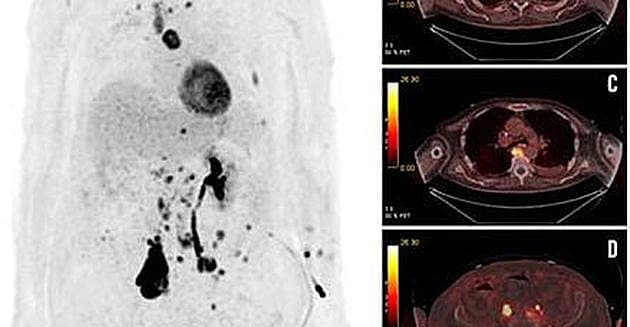

En 74-årig mand med kendt prostatacancer blev indlagt på grund af parese og konfusion. Dagen efter fik han krampeanfald. Avanceret diagnostisk udredning kunne fastslå, at han havde et ikkeerkendt småcellet karcinom, som blev kompliceret med autoimmun encefalitis.